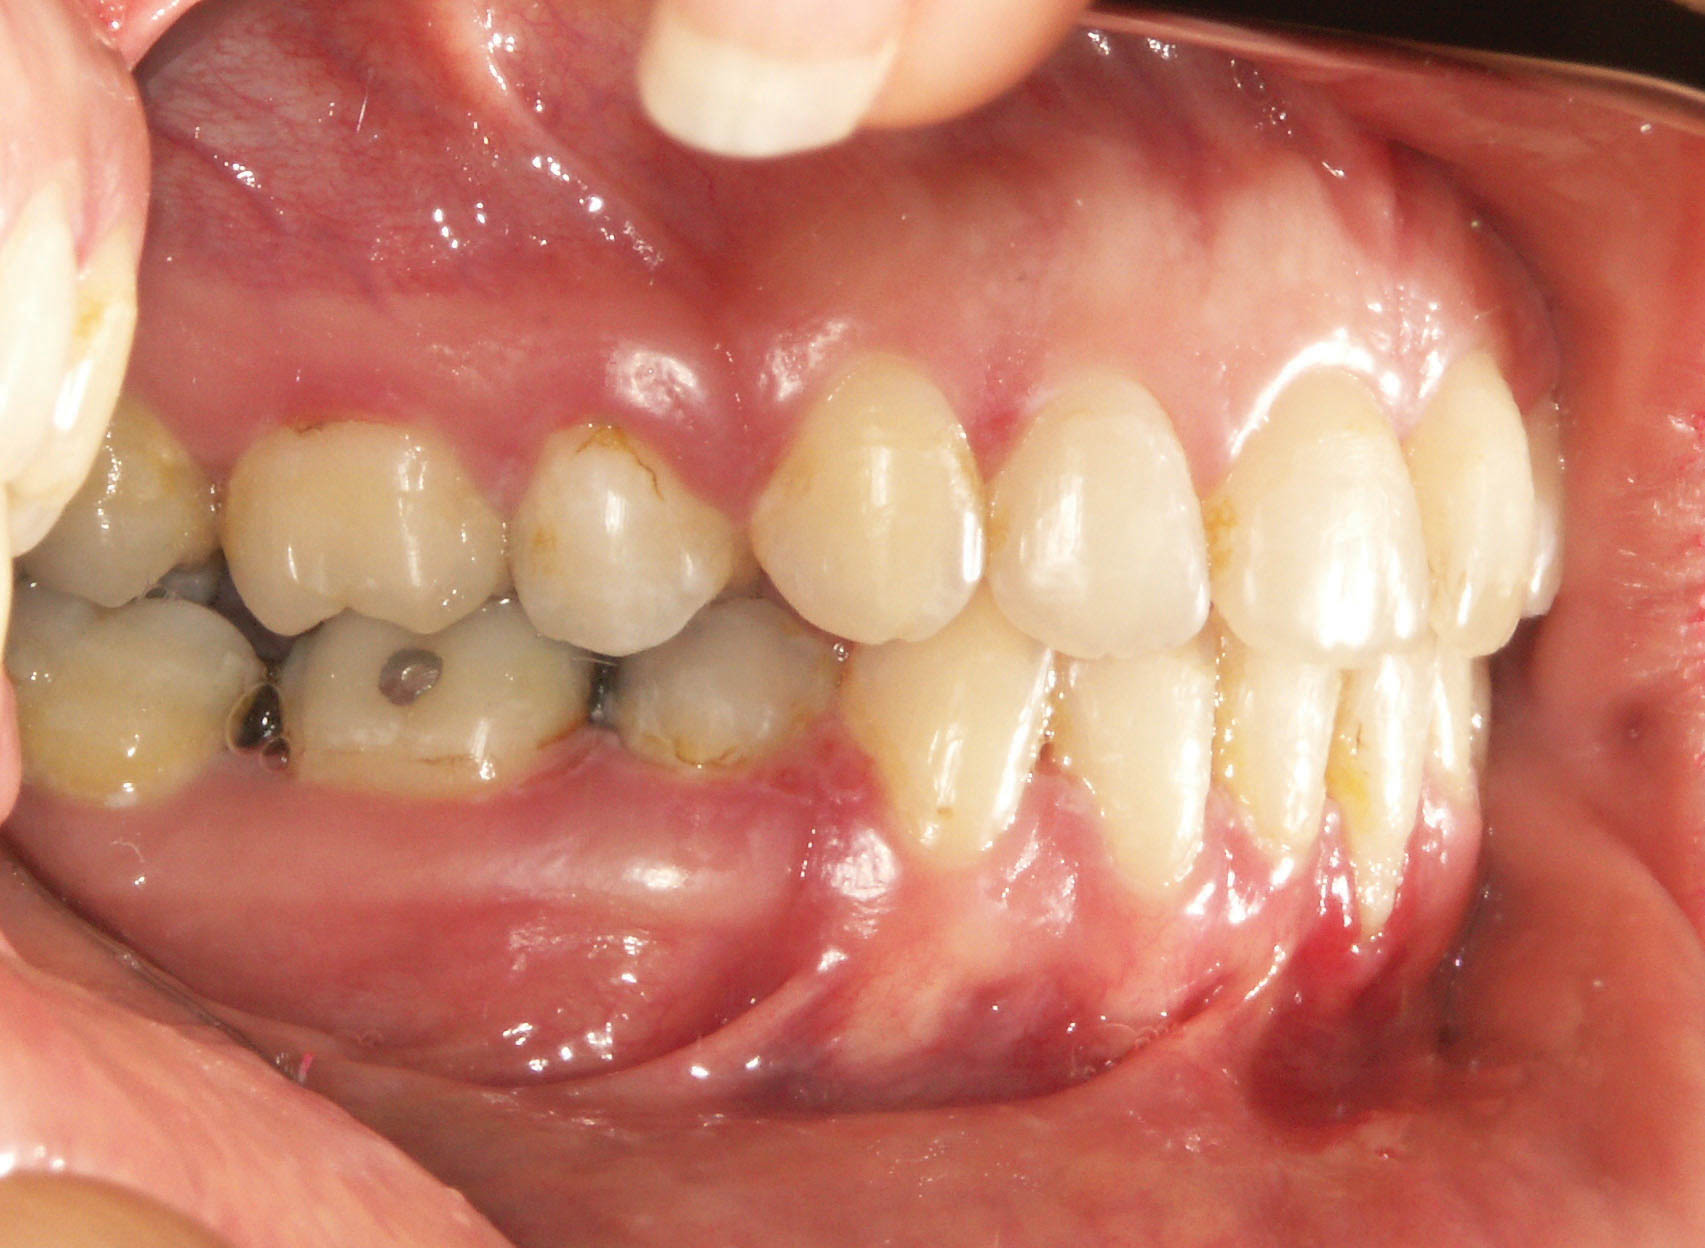

شکل 118-2: اکلوژن کلاسII

مواردی وجود دارد که بخاطر کمبود فضای زیاد یا ارتفاع عمودی زیاد باید پرمولر پایین را بکشید (شکل 118-2).

چون در این بیماران پرمولر پایین کشیده میشود باید از بالا هم بکشید و در نهایت به رابطه کلاسI مولری برسید (شکل 119-2).